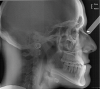

Fig 6. Cephalometric x-ray of patient.

Figure 6